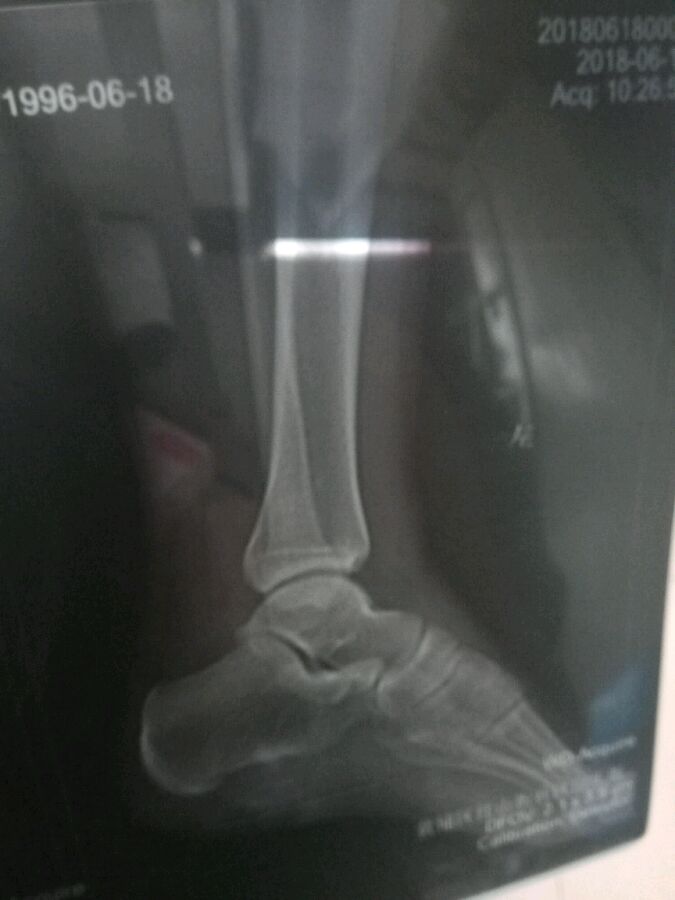

老铁们,帮我看看我脚踝的骨骺线闭合了吗

闭合了,但是还没钙化。

没闭合

回复 扎克拉文💥 :3cm左右吧 主要看腿的

基本闭合,远端的会比近端的先闭合.自然生长周期还没有结束,赶紧运动吧

就目前给的图片的显示,膝关节大概率没有闭合,但是最多也是接近闭合,空间也不会差别非常大,只能说还没有完全闭合而已。

非闭合者,如果还想改善身高,要多做改善身高的运动

已经闭合者,如果还想改善身高,就需要通过特定的训练,才能达到改善的目的,一般的运动效果并不明显

没看到膝关节的图不好判断,这样打个比方吧,假如这是膝关节的骨骺线的话,1-3厘米可能就是自然生长的范围了,当然如果你合理运动的话,同时保持良好的生活习惯,自然空间会高于这个范围。